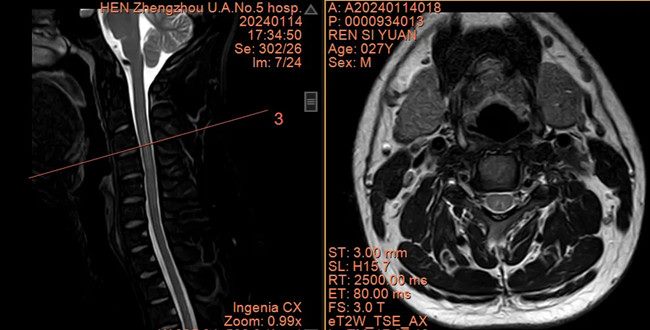

此外,患者的脊髓磁共振成像显示颈胸段脊髓存在多发信号改变,横断面可见“八字征”(通常见于维生素B12缺乏导致的脊髓变性,见下图)。反复追问病史,患者才承认其有吸入N₂O史。结合患者病史、体征、辅助检查,最后诊断为笑气(N₂O)中毒,导致脊髓及周围神经损伤。